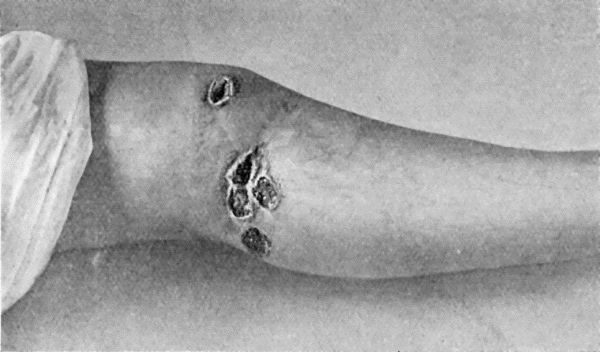

| 17. | Syphilitic Ulcers in region of Knee | 76 |

| 41. | Ulceration in inherited Syphilis | 170 |

| 42. | Tertiary Syphilitic Ulceration in region of Knee and on both Thumbs | 171 |